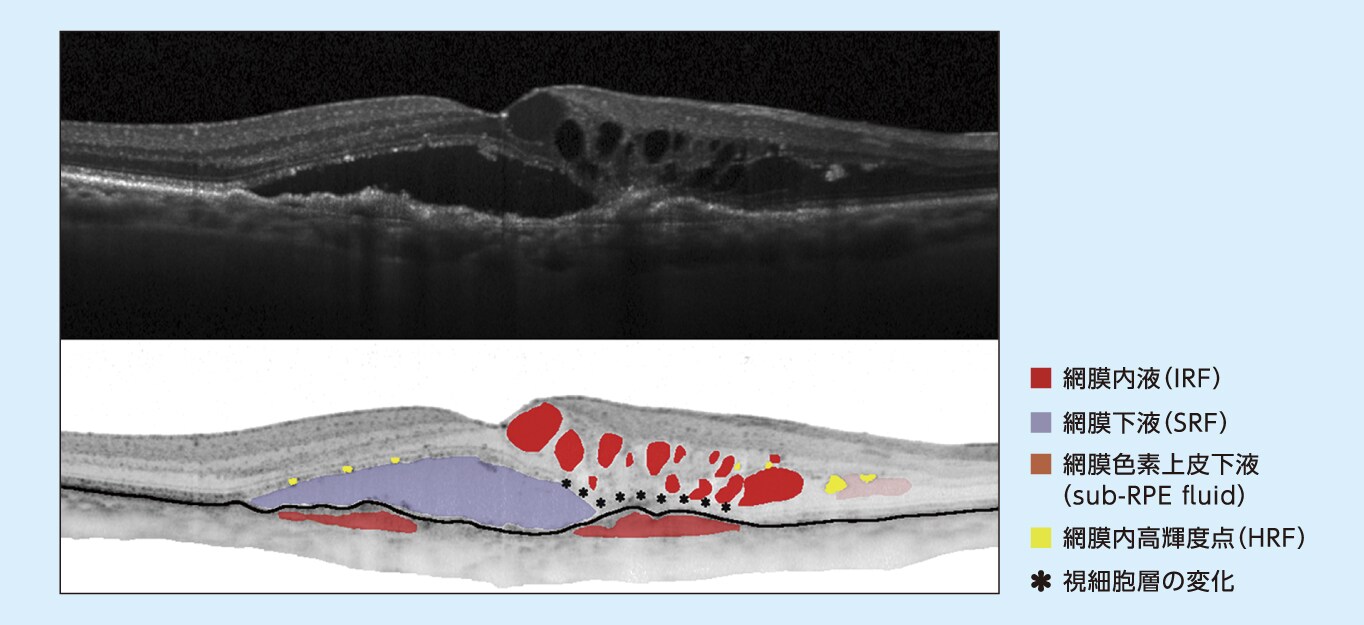

nAMDのOCT画像

OCT(optical coherence tomography):光干渉断層計、IRF(intraretinal fluid)、SRF(subretinal fluid)、RPE(retinal pigment epithelium)、HRF(hyper-reflective foci)